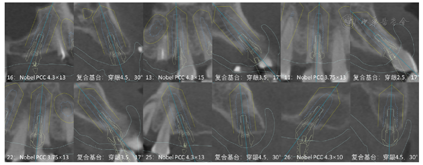

14、15、24-26、34-37、44-47缺失,缺牙区牙槽嵴丰满度一般;16牙探及并可穿通根分叉,但未见根分叉暴露,13残根,11近中颈部、23远中龋坏,33、43牙颈部缺损;31、41松动Ⅲ度,11、12、32、42松动Ⅱ度,16、21-23、33、43松动Ⅰ度,全口散在间隙。全口卫生状况一般,探诊深度5~8 mm,附着丧失6~9 mm,牙龈水肿,探针出血,可探及龈下结石。咬合关系欠佳,口角下垂,面下1/3高度降低,鼻唇角接近90°。上唇活动度较小,中位笑线(图1)。颞下颌关节检查无明显异常,开口型正常,开口度三横指。放射学检查:术前全景片显示13残根,16牙根尖牙槽骨吸收,11、23牙远中颈部见低密度影,余留牙牙周膜间隙增宽,周围牙槽骨水平吸收至根尖1/3-1/2(图2)。术前CBCT截图显示13牙残根,12、21、22、31、32、33、43牙颈部见不同程度楔状缺损。31、41、42牙周围牙槽骨水平吸收至根尖1/3,16、12、11、21-23、32、33、43牙牙周膜增宽,周围牙槽骨水平吸收至根尖1/2不等(图3)。

治疗过程:(1)术前准备:①藻酸盐取初印模,制作个性化托盘(图4);②用个性化托盘取硅橡胶终印模,灌制终模型;③制作光固化树脂

架;④排牙,制作放射导板(图6A);⑤试戴放射导板(图6B~D),拍摄两次CBCT(患者佩戴放射导板拍摄CBCT以及放射导板单独拍摄CBCT)。(2)方案设计:①将两次CBCT获取的DICOM数据导入种植设计软件重叠(图7),以修复为导向指导上下颌种植体位置摆放(图8、图9);②生成并打印手术导板(图10)。(3)利用手术导板和导板锁,翻制模型,制作临时修复体(图11)。(4)一期手术过程:铺巾消毒,局麻后拔除上下颌余留牙,搔刮拔牙窝内炎性肉芽组织,于34-36、44-46区牙槽嵴顶近远中向切开牙龈,翻瓣。就位并固定手术导板,于11、13、16、22、25、26、32、34、36、42、44、46定点,按术前设计方案植入NobelParallelTM ConicalConnection种植体。除26区种植体外,其余种植体初期稳定性均达到35N.cm以上,就位复合基台,戴入保护帽,修整牙龈黏膜,缝合牙龈(图12A~F)。术后拍摄全景片(图13)。次日复诊,取下保护帽,戴入预制的临时修复体,调合(图12G)。